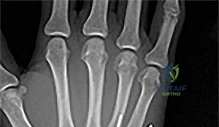

Question 17:

A 25-year-old male injures his midfoot when falling from a horse with his foot caught in the stirrup. Radiographs show a widening of the space between the base of the 1st and 2nd metatarsals. Which ligament is primarily ruptured in a classical Lisfranc injury?

Correct Answer: Ligament connecting the 2nd metatarsal base to the medial cuneiform

Explanation:

The Lisfranc ligament connects the medial cuneiform to the base of the second metatarsal. It is a critical stabilizing structure of the midfoot, and its rupture leads to instability.